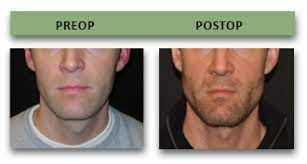

4mm downgraft in total of the lower third

4mm anterior downward custom wedge shaped genio

3 mm posterior genio

10mm ramus widening - 5mm each sided

a combo of clockwise and counter clockwise rotation to fix my canted mandible

3mm of lefort 1

Im not getting a big lefort movement. My bimax will be focused on more vertical height then forward growth. Since I’m not getting a big lefort movement should I still ask for the alar synch to avoid as much as possible any alar base expansion.